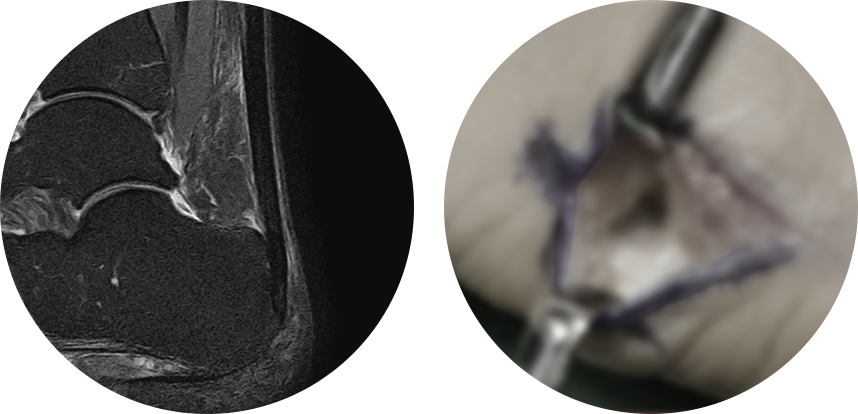

비수술적으로 치료가 되지 않는 만성 족저근막염에 대한 치료로, 2mm 정도의 소형 관절 내시경을 이용하여

족저근막을 부분 유리하여 수술 후 통증이 적고 일상생활로의 회복이 빠릅니다.

MRI 사진의 빨간 포탈을 이용하여 족저근막을 유리하여 터놓은 후, 시간이 지나면서 자연스럽게 연결되어 늘어나는 효과가 나타나게 됩니다.

비수술적으로 치료가 되지 않는 만성 아킬레스건염에 대한 치료로, 가장 문제가 되는 부위에 최소 절개를 통해

아킬레스건 주변 염증 조직을 제거하며, 수술 후 통증이 적고 일상생활로의 회복이 빠릅니다.

* 환자에게 받은 소중한 자료입니다.

아킬레스건염이 만성 중증인 경우 다음과 같이 개방형 건활액막절제술을 통해 염증 조직 및 퇴행성 조직을 제거해줄 수 있으며,

부착성 아킬레스건염의 경우 재부착이 필요할 수도 있습니다.